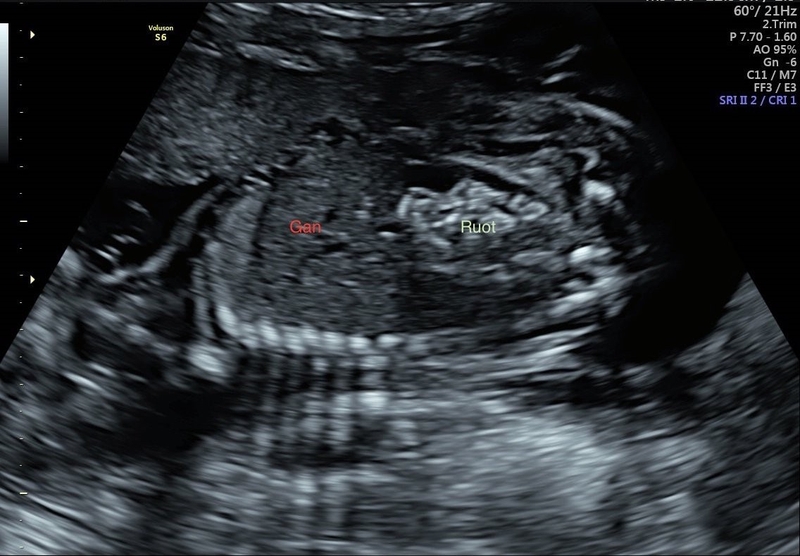

Ruột phản âm sáng độ 2 là gì và có nguy hiểm không?

Ruột phản âm sáng độ 2 trong siêu âm thai nhi là một khám phá quan trọng. Dấu hiệu này cho biết ruột của thai nhi có sự phản âm sáng hơn so với mức bình thường, thường chỉ xuất hiện trong một số trường hợp rất hiếm (0.2-1.4% phụ nữ mang thai). Điều này có thể là một dấu hiệu tích cực, tượng trưng cho sự phát triển và sức khỏe của thai nhi, nhưng cũng có thể là dấu hiệu của một số bệnh lý. Việc tìm hiểu thêm ruột phản âm sáng độ 2 là gì và nguyên nhân dẫn đến tình trạng trên là rất quan trọng.

Ruột phản âm sáng độ 2 là một dạng biểu hiện được phát hiện thông qua siêu âm. Trong quá trình siêu âm thai, khi hình ảnh phản ánh của ruột được tạo ra, thường thì ruột sẽ có mức độ phản ánh sáng trung bình. Tuy nhiên, nếu ruột phản ánh sáng hơn bình thường, tạo ra một điểm sáng tương phản, thì được xem là ruột phản ánh sáng độ 2.

Tóm lại, ruột phản âm sáng độ 2 là một biểu hiện trong siêu âm, cho thấy ruột thai nhi có độ phản ánh sáng cao hơn so với bình thường. Để hiểu rõ hơn về tác động và tình trạng của thai nhi, cần tìm hiểu thêm thông tin từ một bác sĩ chuyên gia và tiến hành các xét nghiệm và siêu âm bổ sung.